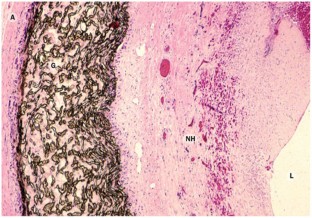

Roy-Chaudhury, P. et al. Neointimal hyperplasia in early arteriovenous fistula failure. Am. J. Kidney Dis. 50, 782–790 (2007).

Roy-Chaudhury, P. et al. Cellular phenotypes in human stenotic lesions from haemodialysis vascular access. Nephrol. Dial. Transplant. 24, 2786–2791 (2009).